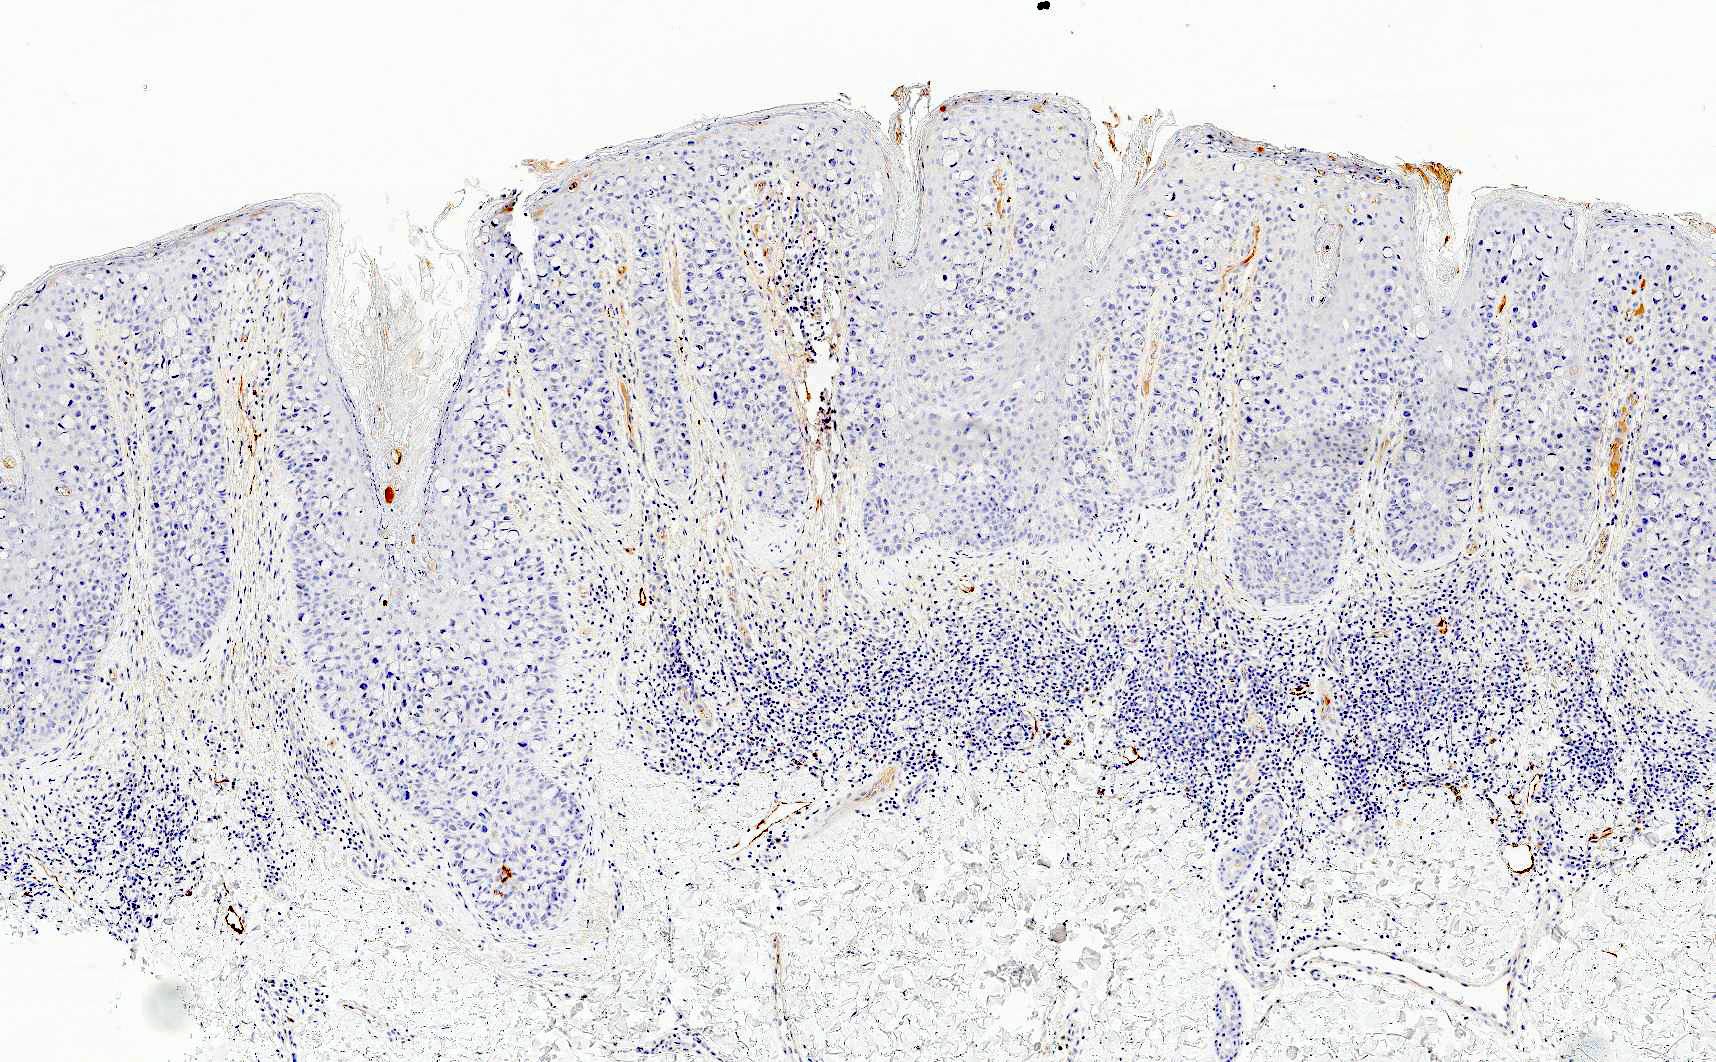

Microscopic (histologic) images

Contributed by Priya Nagarajan, M.D., Ph.D. and Lucy Ma, M.D.

Positive stains

- Primary and secondary Paget disease: CAM 5.2, EMA, CEA, mucicarmine, periodic acid-Schiff (PAS)

- Primary Paget disease: CK7, GATA3, GCDFP-15, androgen receptor, p16 (weak to moderate) (Am J Clin Pathol 2000;113:572)

- Secondary Paget disease, anorectal primary: CK20, CDX2, SATB2

- Secondary Paget disease, urothelial primary: CK7, CK20, GATA3, uroplakin III, p63

- Secondary Paget disease, cervical primary: CK7, PAX8, p16 (block positive), high risk HPV ISH

Negative stains

- Primary and secondary Paget disease: HMB45, MelanA, SOX10, MITF, p63, p40, CK5/6, ER and PR (Am J Clin Pathol 2000;113:572)

- Primary Paget disease: CK20

- Secondary Paget disease, anorectal primary: CK7, GATA3, GCDFP-15, uroplakin III

- Secondary Paget disease, urothelial primary: GCDFP-15

- Secondary Paget disease, cervical primary: CK20, GATA3, GCDFP-15